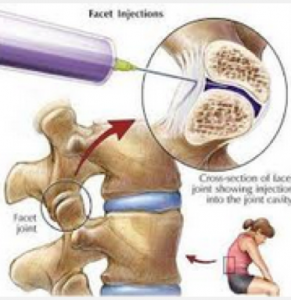

- 脊椎小關節面注射

脊椎小關節面注射